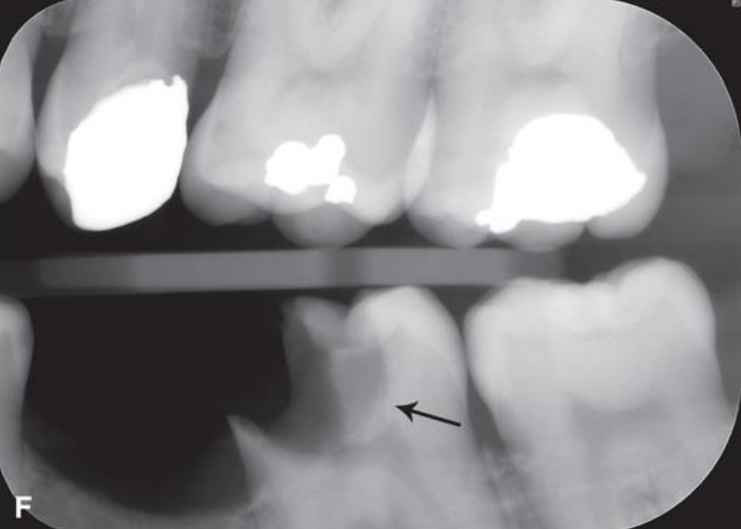

classify this lesion based on the ADA caries classification system

D3